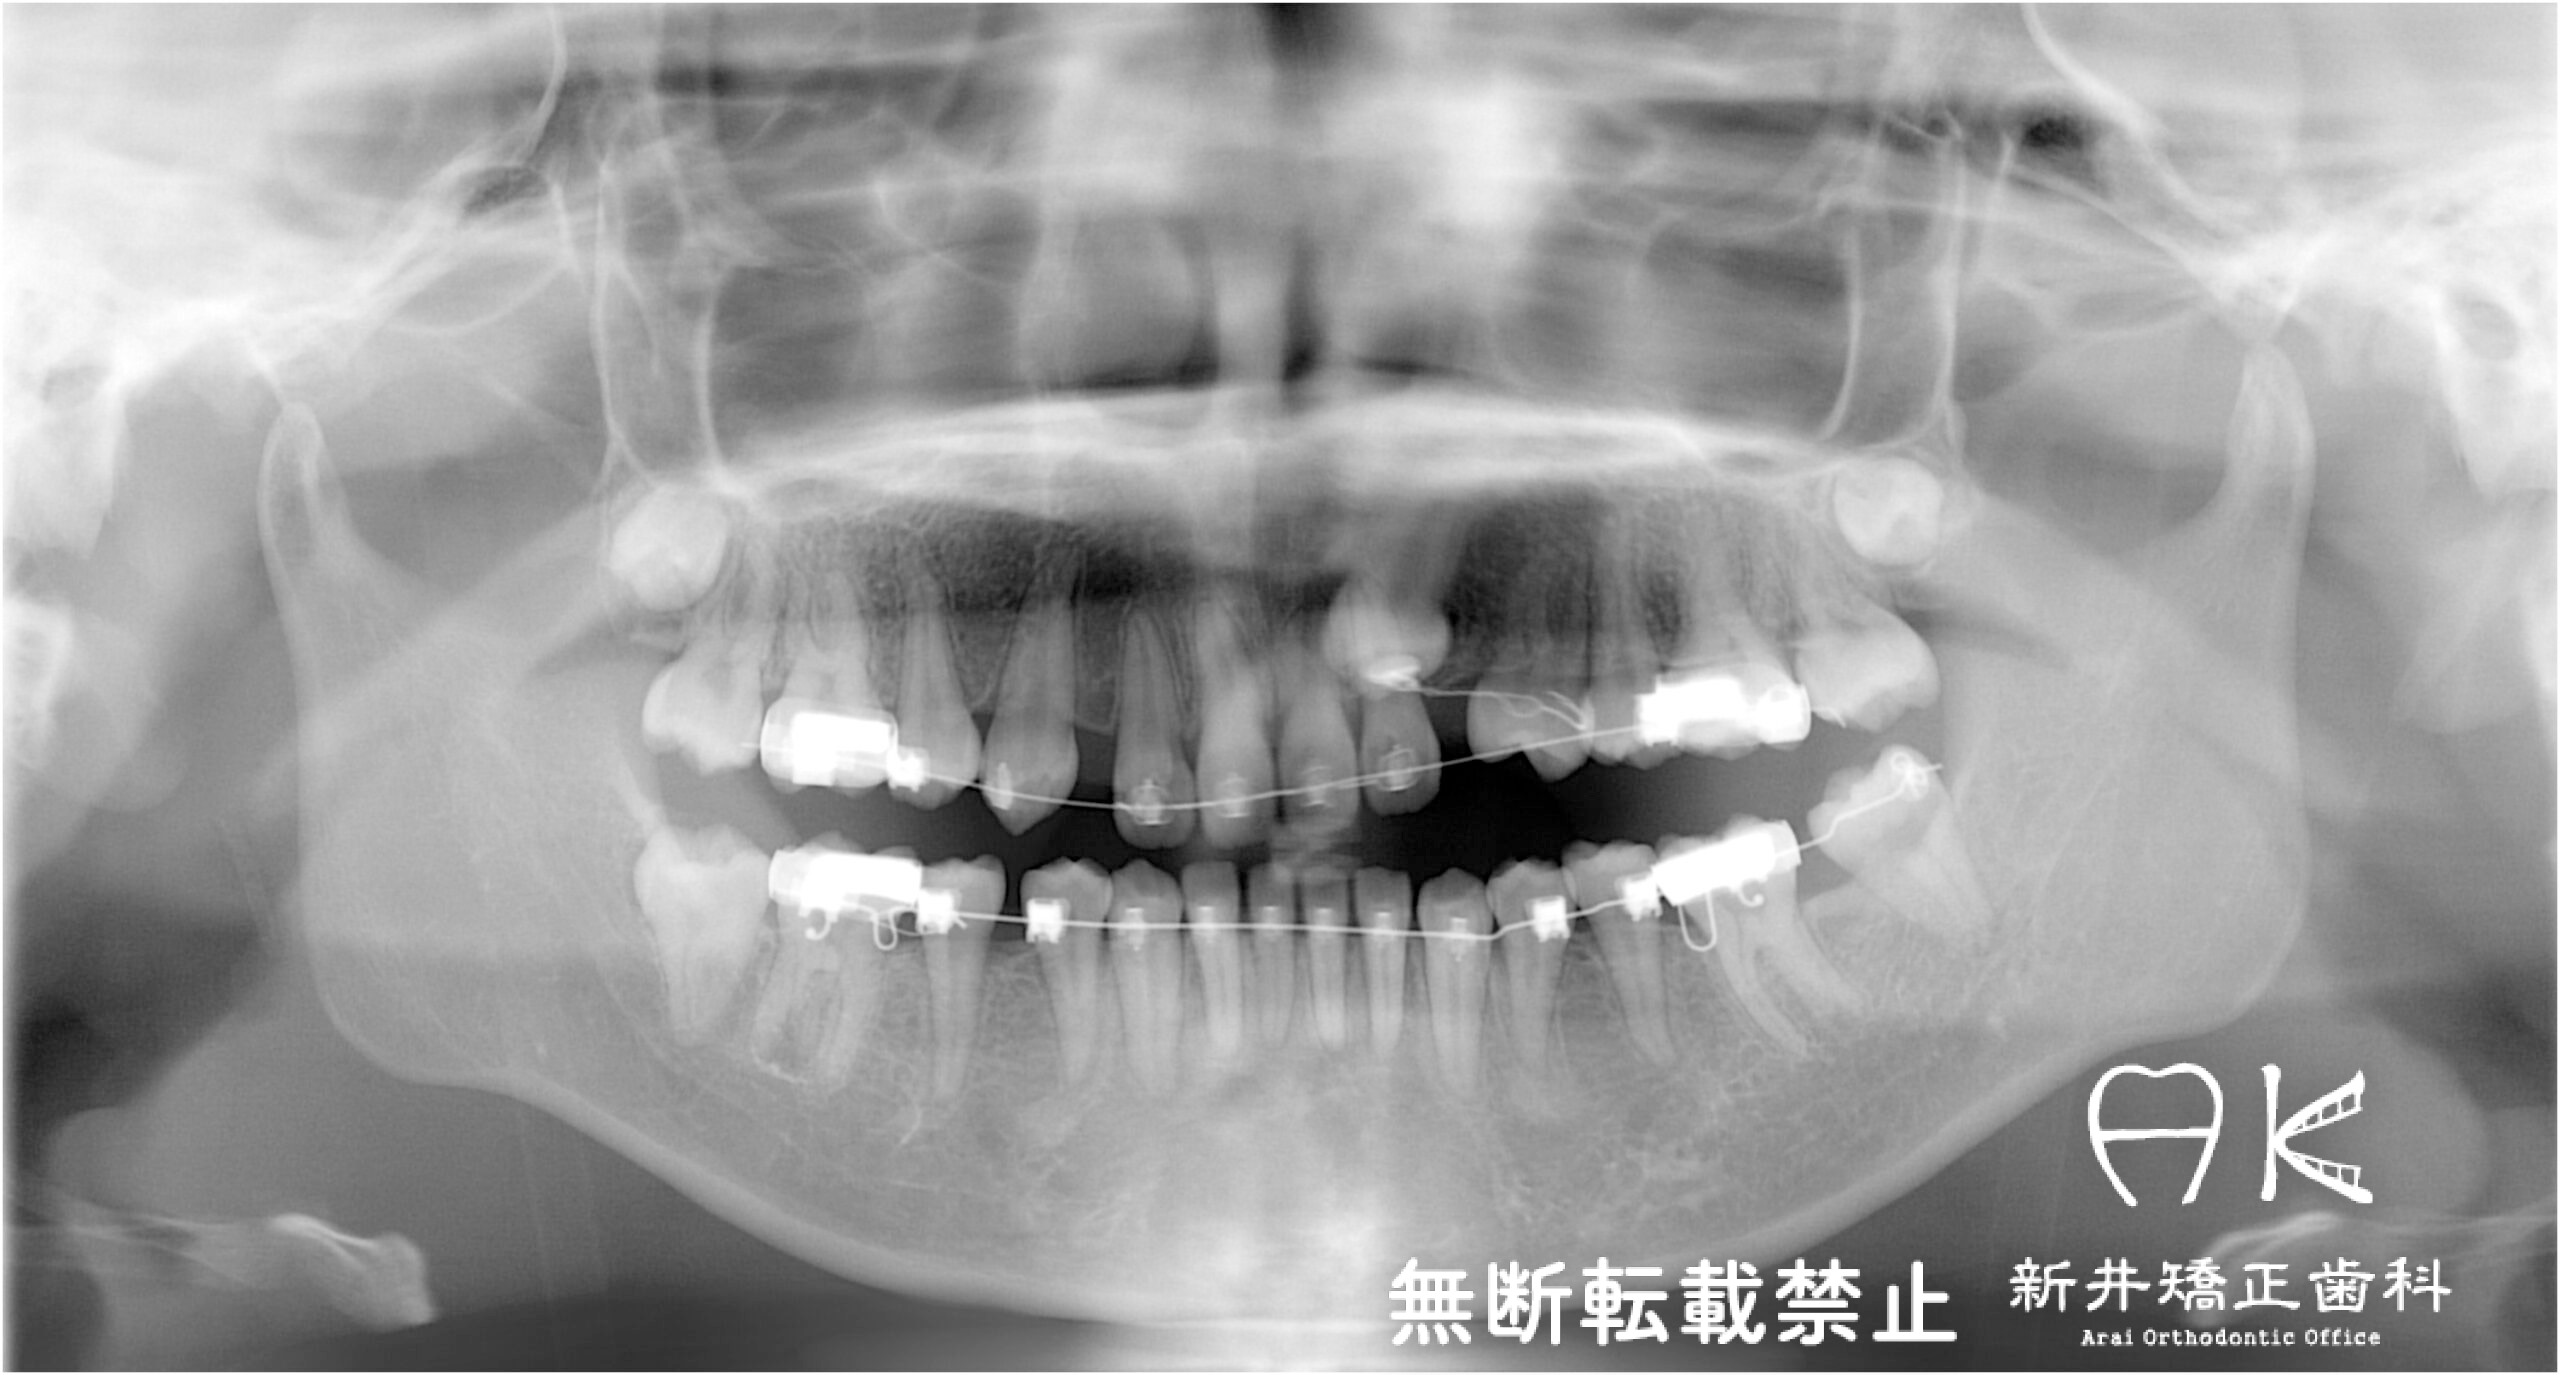

治療中

![]() | ||

![]() | ![]() | ![]() |

![]() |